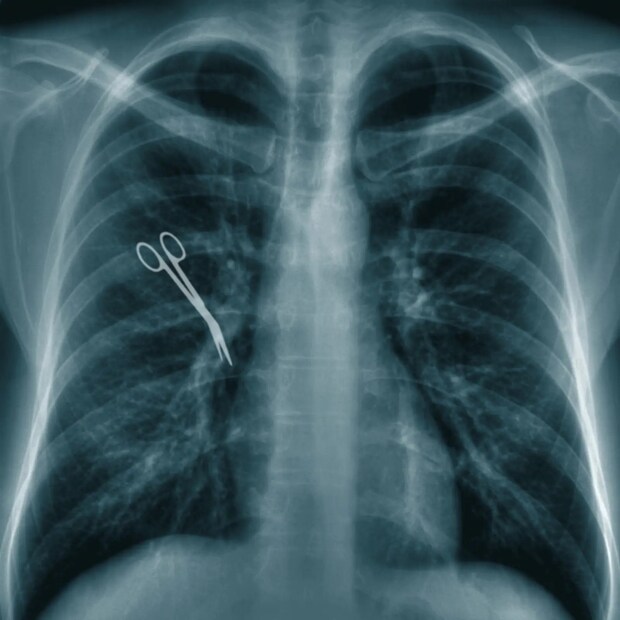

জীবনের কঠিনতম স্বাস্থ্য সমস্যায় চিকিৎসকের উপর নির্ভর করা ছাড়া কোনও উপায় থাকে না। বিশেষ করে অস্ত্রোপচারের সময়। অপারেশন টেবিলে সবটুকুই হাতে থাকে চিকিৎসকদের দলের। সার্জনের উপর রোগীর সম্পূর্ণ আস্থাই কাম্য। কিন্তু মাঝে মাঝেই নানান ঘটনা থেকে এই আস্থা টলমল করে ওঠে। চিকিৎসকদের উপর চোখ বন্ধ করে বিশ্বাস করার ঘটনা বারে বারেই গোঁত্তা খায় নানান অবহেলার উদাহরণে। চিকিৎসকদের গাফিলতিতে বেঘোরে প্রাণ হারাতে পারেন রোগী। ঠিক যেমন ঘটেছে ভেনেজুয়েলায়। অস্ত্রোপচারের সময় সার্জনরা রোগীর পেটের ভিতরেই কাঁচি রেখে ভুলে যাওয়ায় মৃত্যু হয়েছে তাঁর।

দ্য মিরর জানিয়েছে, মৃত ইভান শ্যাভেজ পেটের অপারেশনের জন্য ভেনেজুয়েলার দ্বিতীয় বৃহত্তম শহর মারাকাইবোর বিশ্ববিদ্যালয় হাসপাতালে ভর্তি হন। ডাইভার্টিকুলার ফুলে যাওয়ায় চিকিৎসকরা অস্ত্রোপচার করতে নির্দেশ দেন। প্রাথমিকভাবে অপারেশনটি সফলও হয়েছিল। কিন্তু অপারেশনের পরপরই, রোগীর পেটে ব্যথা এবং খেতে এবং মল মূত্র ত্যাগে নানান অসুবিধা হতে শুরু করে। চিকিৎসকরা তাঁকে বিভিন্ন চিকিৎসার পরামর্শও দেন।

হাসপাতালের একজন চিকিত্সক ডাঃ ফ্রেডি পাচানো অ্যারেনাস গত সপ্তাহে ট্যুইটে জানান, রোগীর মৃত্যুর সঙ্গে জড়িত সন্দেহে আটক তাঁর সহকর্মী জেরার্ডো নুনেজ এবং লুইস গোমেজকে মুক্তি দেওয়া হয়েছে। তাঁর দাবি, “একজন মানুষের জীবন বাঁচানোর জন্য কোনও কাজের পরে ইচ্ছাকৃতভাবে তাঁকে হত্যার জন্য কাউকে দোষারোপ করা অসম্ভব।” পরিবারের অবশ্য দাবি, চিকিৎসকরা তাঁদের গাফিলতি আড়াল করার জন্যই সবকিছু ঠিকঠাক থাকার ভান করেছিলেন।